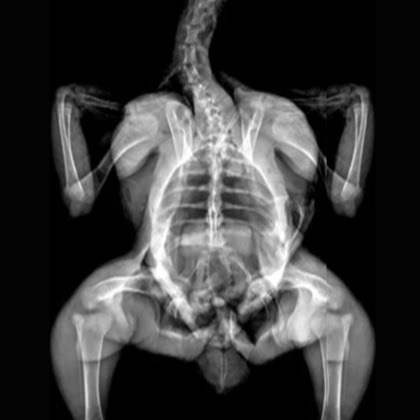

Marmosets. Image Credit: Scintica Instrumentation Inc

X-Ray Attenuation Image - Rat. Image Credit: Scintica Instrumentation Inc

Color Image - Rat. Image Credit: Scintica Instrumentation Inc

Bone Mineral Density Image - Rat. Image Credit: Scintica Instrumentation Inc